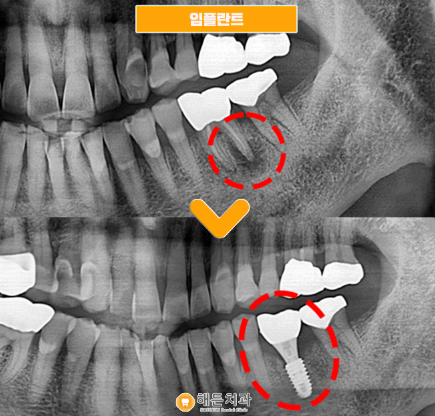

천안아산치과 해든치과에서 임플란트 식립을 위해 말끔히 발치한 파노라마 사진입니다.

발치 후에 염증이 나타나 잇몸뼈가 많이 녹아있는 모습이 더욱 잘 나타나 있습니다.

천안아산치과에서는 염증조직을 모두 제거한 후 뼈이식과 함께 임플란트 픽스처를 함께 식립했습니다.

뿌리 염증이 있을 때 뼈이식을 진행하는 이유는 바로 안정적인 식립을 위해서 입니다.

염증 때문에 잇몸뼈가 녹은 상태에서 무리한 임플란트 식립을 시도하면 임플란트 픽스처가 제대로 유착되지 않을 수 있습니다.

그렇게 되면, 치료기간은 더 길어지게 되어 불편함은 더더욱 커지게 됩니다.

따라서 환자분같이 뿌리 염증이 있을 때 뼈이식을 해주어 부족한 잇몸뼈를 충분히 만들어준 뒤 안정적인 식립이 가능하도록 진행해야 합니다.

위의 사진과 같이 잇몸뼈가 제대로 만들어져 있고 임플란트 픽스처와 안정적으로 결합되었습니다.

따라서 해든치과에서는 사진뿐만 아니라 치조골과 잘 결합되었는지 수치로도 확인하는 과정을 거치고 있습니다.

환자분 또한 적정수치인 것을 확인하고 보철물과 픽스처를 이어주는 어버트먼트 또한 연결하여 크라운을 올려 마무리했습니다.